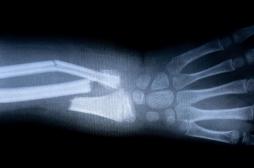

J ai Mal Bras et mains Bras et mains Tête et cou Torse et haut du dos Jambes et pied